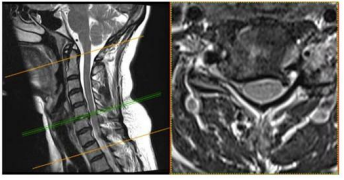

Uma paciente de 47 anos de idade apresenta quadro de

cervicobraquialgia direita há cerca de três meses, associada a

parestesia no membro superior direito, que se estende até

mão, principalmente nos dedos indicador e polegar. Ao

exame fisico, nota-se leve redução do reflexo

braquioestilorradial. O teste de Spurling foi positivo à direita.

Observou-se ausência de paresias.

No citado caso clínico, foi solicitada uma ressonância magnética cervical, conforme representado nas figuras. Esse exame evidencia uma